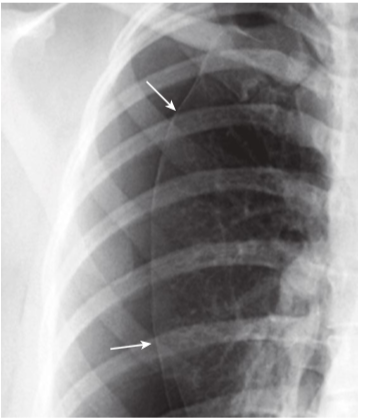

Hydropneumothorax.

hydropneumothorax produces an air-fluid level in the hemithorax marked by a straight edge and a sharp, air-over-fluid interface when the exposure is made with a horizontal x-ray beam (black arrows). This person was stabbed in the right side and there is a moderately large pneumothorax as shown by the visceral pleural white line (white arrows).